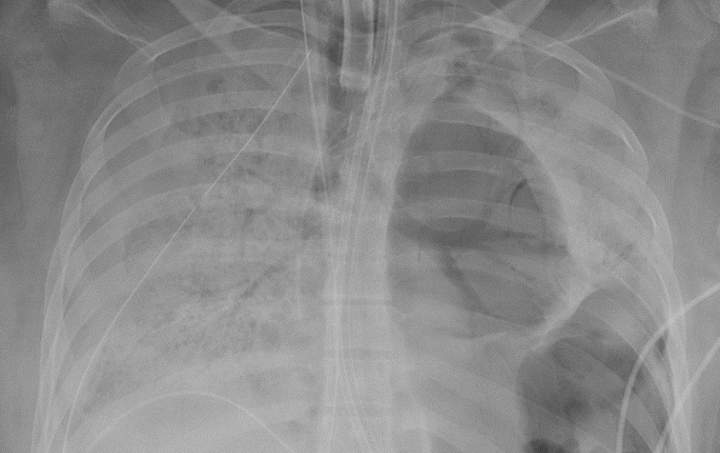

COVID-19 attacked one lung, cancer the other. A double transplant saved himOne lung ravaged by COVID-19, the other damaged by lung cancer — this was the daunting reality facing 56-year-old Arthur Gillespie, a former police captain from Chicago.HealthMay 13, 2024

Woman’s lungs look like ‘Swiss cheese’ after COVID-19, gets double transplantA young woman's lungs were damaged so badly by the novel coronavirus that she needed a double lung transplant, a U.S. hospital said.HealthJun 15, 2020